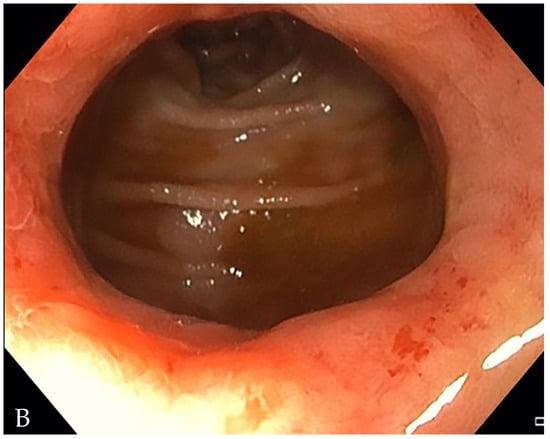

6. Is the Stricture Fibrotic or Inflammatory?